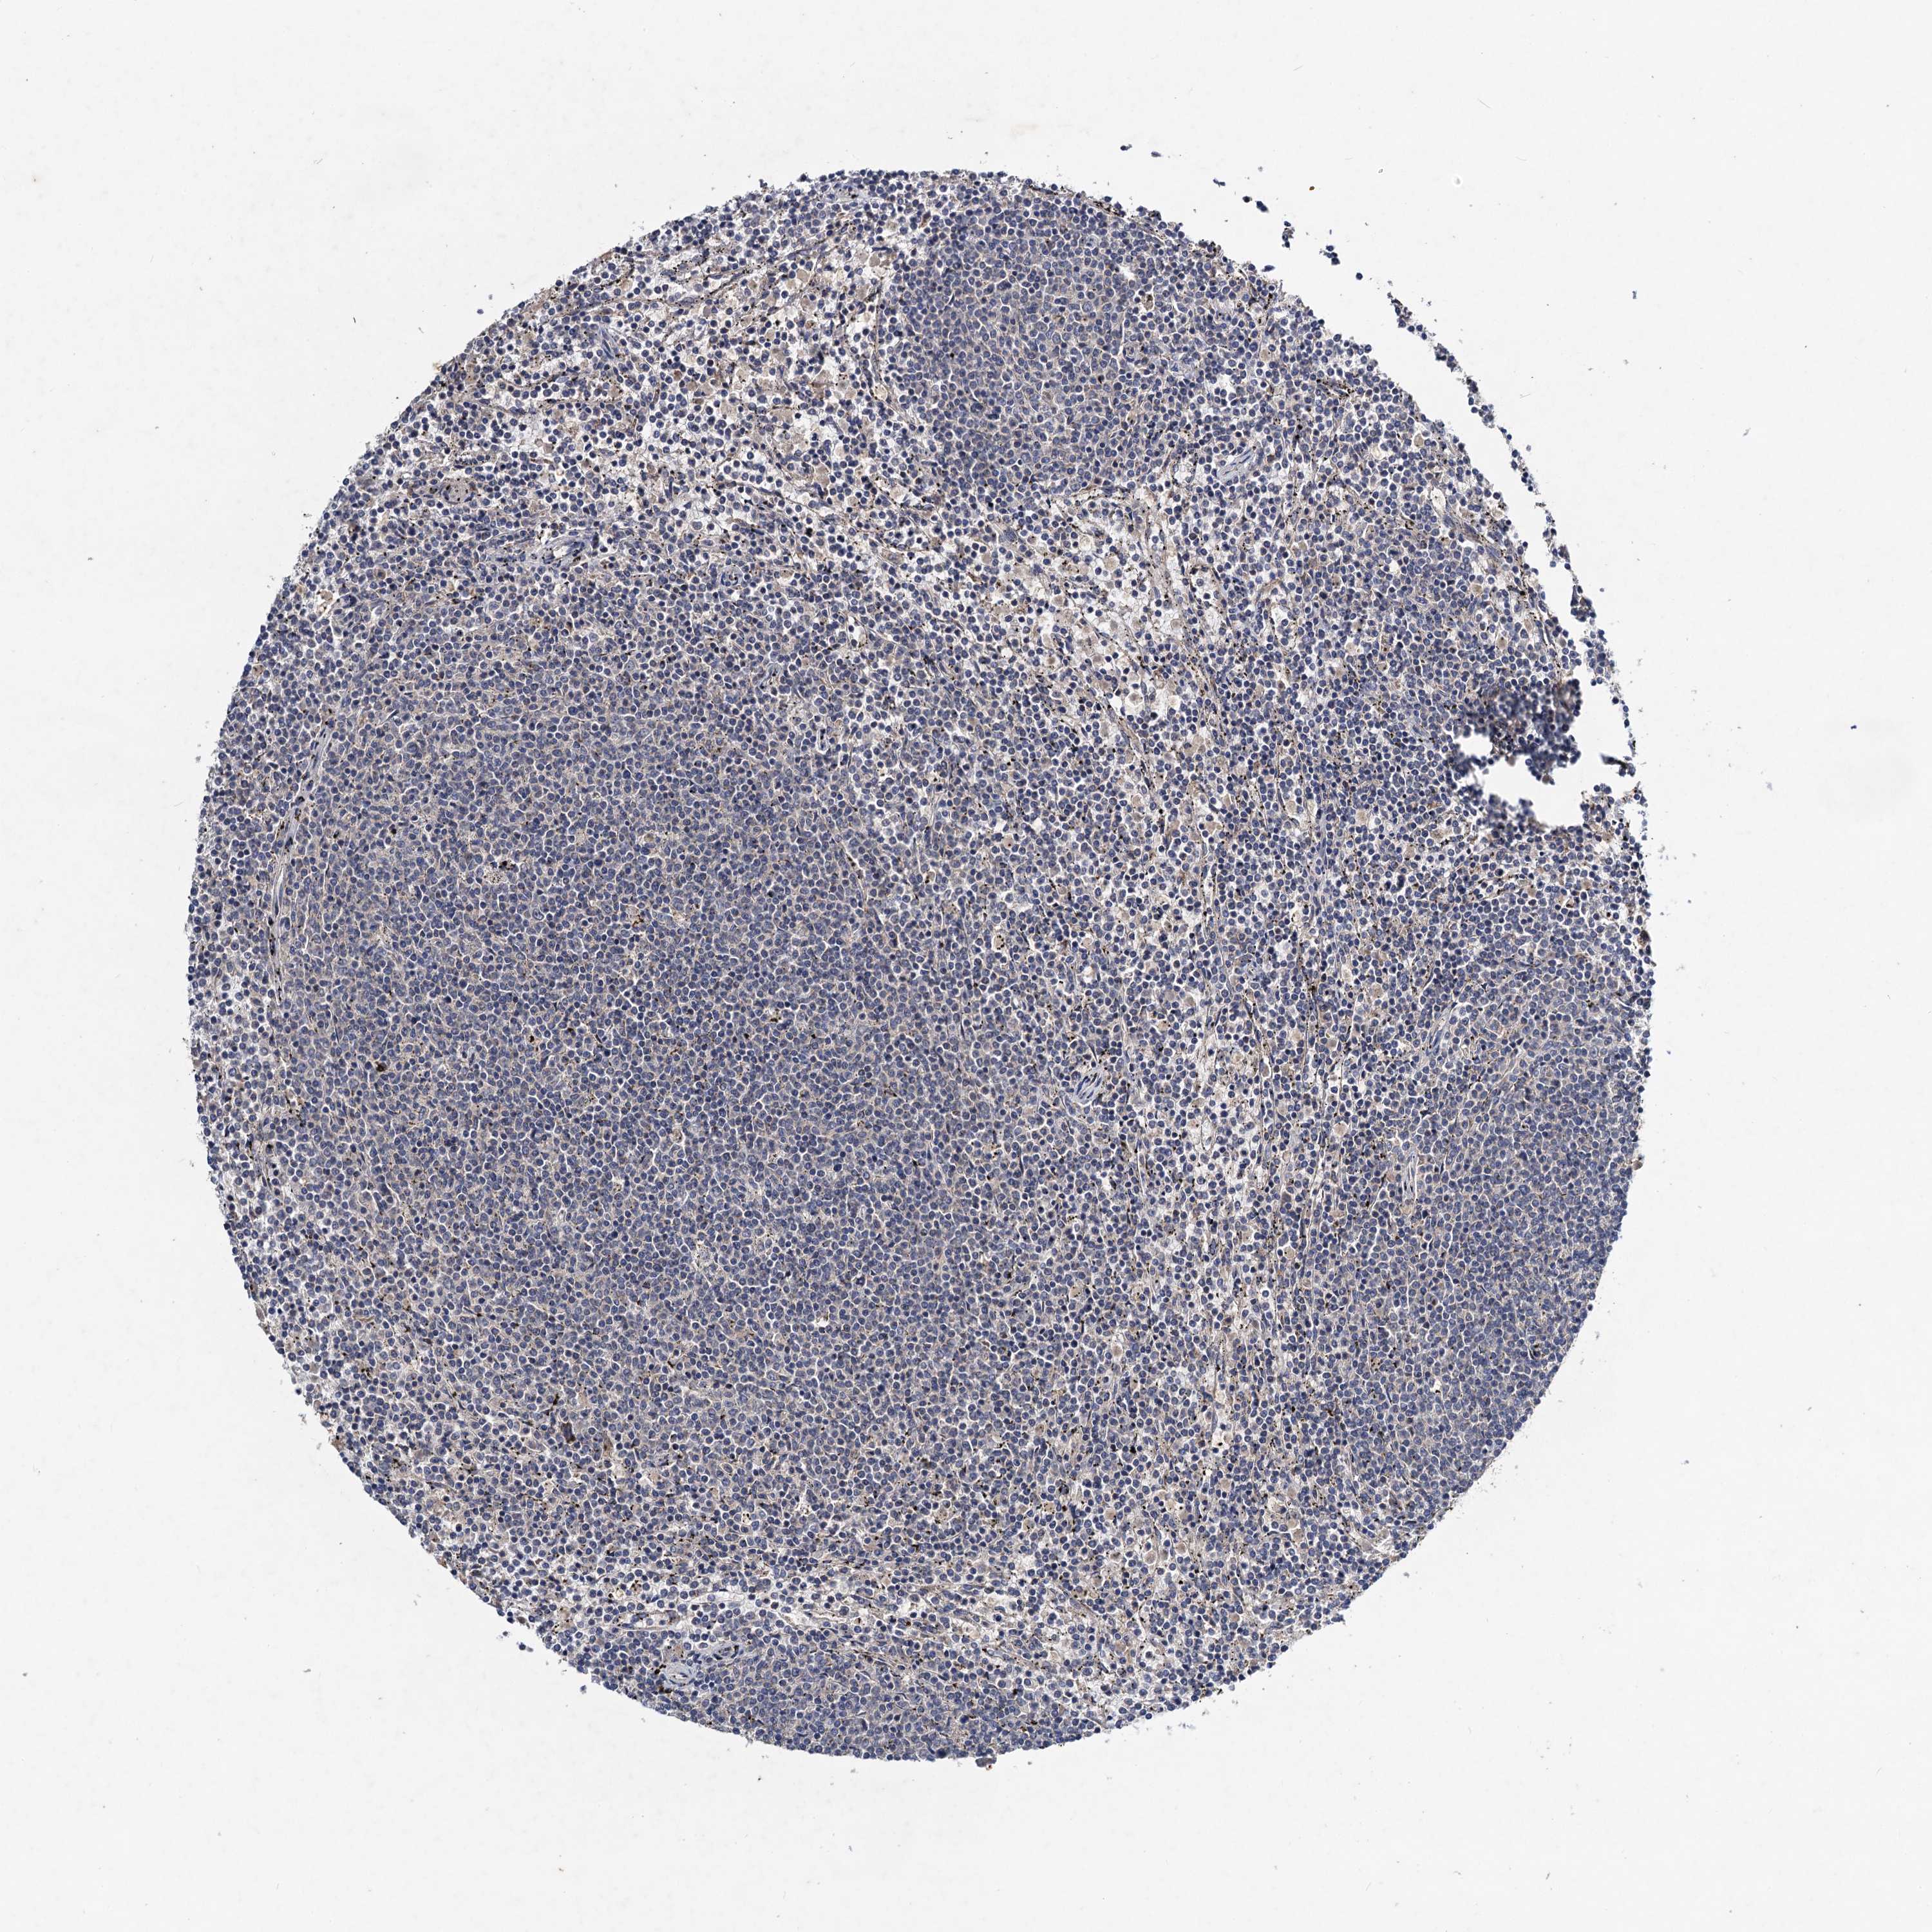

CANCER LYMPHOMA Show tissue menu

LYMPHOMA - Protein expressioni

A mouse-over function shows sample information and annotation data. Click on an image to view it in a full screen mode. Samples can be filtered based on level of antibody staining by selecting one or several of the following categories: high, medium, low and not detected. The assay and annotation is described here.

Antibody stainingi

Antibody staining in the annotated cell types in the current human tissue is reported as not detected, low, medium, or high, based on conventional immunohistochemistry profiling in selected tissues. This score is based on the combination of the staining intensity and fraction of stained cells.

Each image is clickable and will lead to virtual microscopy that enables deeper exploration of all samples and also displays staining intensity scores, fraction scores and subcellular localization as well as patient and tissue information for each sample.

Antibody HPA040978

Staining

High

Medium

Low

Not detected

Intensity

Strong

Moderate

Weak

Negative

Quantity

>75%

75%-25%

<25%

None

Location

Nuclear

Cytoplasmic/membranous

Cytoplasmic/membranous,nuclear

Hodgkin's disease, NOS

Malignant lymphoma, non-Hodgkin's type, High grade

Malignant lymphoma, non-Hodgkin's type, Low grade